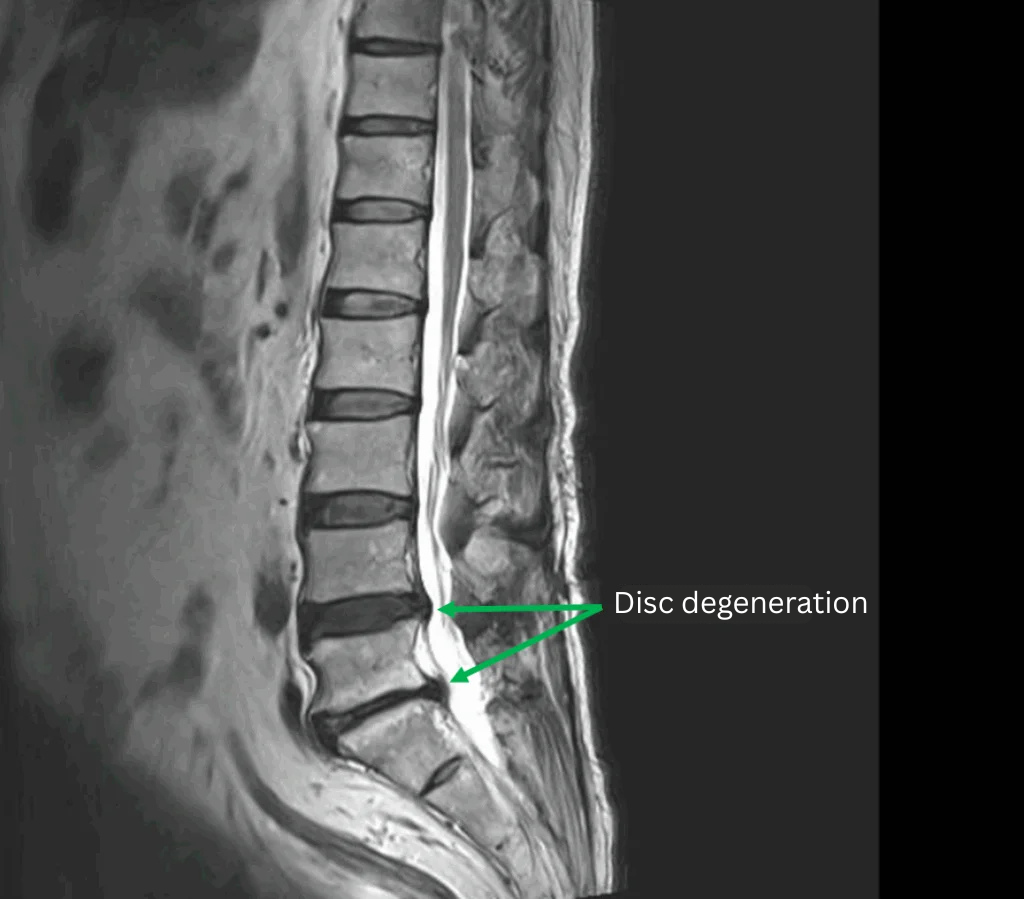

Imaging and findings

| Level | Findings |

| L4/L5, L5/S | Disc degeneration |

| L4/L5 | Lumbar disc herniation |

The above findings were also observed on the imaging.

・The disc herniation at L4/L5 is the most likely cause of the patient’s symptoms.

・The foraminal stenosis at L5/S, caused by disc degeneration, may also be contributing to the symptoms.